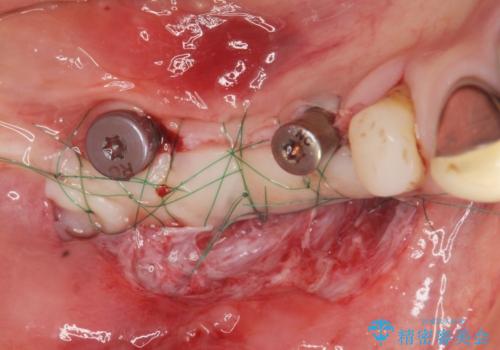

狭小な歯槽骨に対するインプラント治療

- 歯を失い噛めないこと、骨の幅が狭く他院でインプラント治療が難しいと断られ、当院でのインプラント治療が可能かどうか相談来院されました。

骨の造成、角化歯肉の移植を行いインプラント周囲の環境を整えた治療を計画します。

遊離歯肉移植術(硬い歯ぐきのインプラント周囲への移植)を行ったことで、炎症に強く歯ブラシのしやすい環境をインプラント周囲に整えることができました。